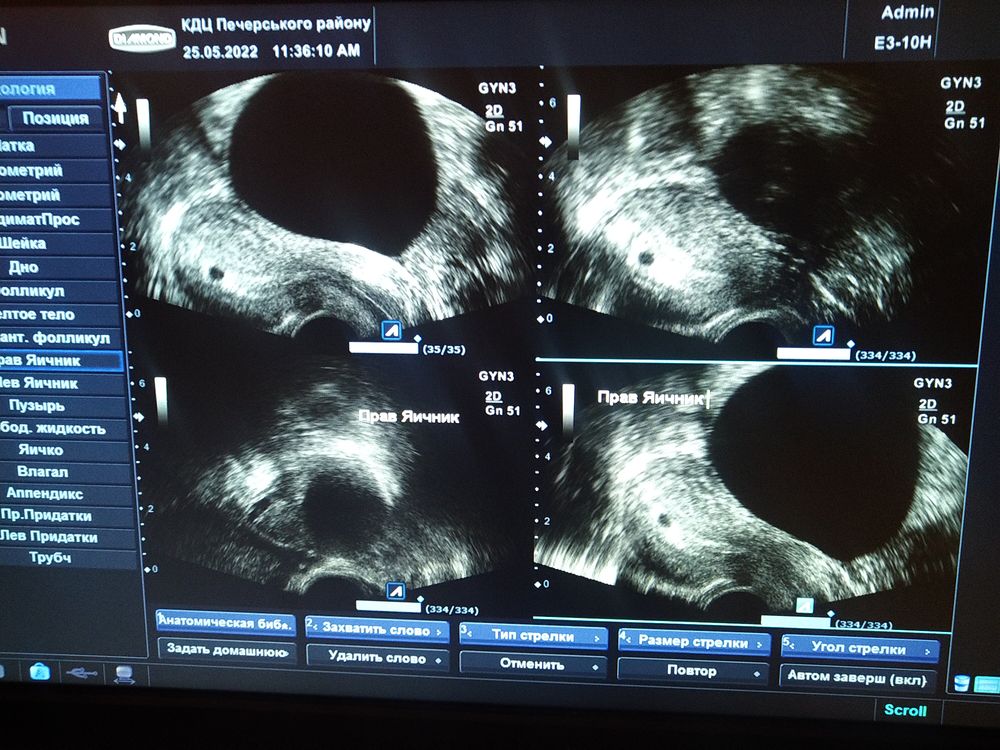

Ух девочки,всем привет,меня не было какое то время,я переживала очень,но сейчас немного попустило.Была несколько раз на УЗИ. Сейчас опять пойду в пн.Вообщем я лежала на кушетке и не могла сдержать слезы,когда мне сказали по УЗИ 4 недели,маточная беременность.Есть проблема с вялорастущим ХГЧ, и огромной кистой.Но меня как то попустило,я спокойна,готова к любому исходу.Теперь му ждём сердечка♥️И объявим после родным